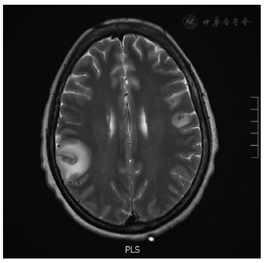

入院第13天复查CT提示右肺多发结节伴上叶空洞影(新发),考虑革兰阳性球菌或真菌感染,予联合抗感染治疗(利奈唑胺+头孢他啶+卡泊芬净+伏立康唑+甲硝唑)。入院第15天出现右侧嘴角抽动,双眼上翻,癫痫发作,复查头颅CT提示右侧颞顶叶低密度影,完善头颅MRI见(右额颞顶叶、双侧枕叶、左额叶大脑皮质肿胀,见多发斑片状T1W1灰,T2W1灰低,Flair像周围见T1W1低,T2W1高信号影环绕,增强扫描见不均匀强化,图1),考虑血源性脑脓肿,继续同上抗感染治疗,加用丙戊酸钠、左乙拉西坦抗癫痫,于入院第16、17天行腰穿检查,脑脊液压力均为150 mmH2O(1 mmH2O=0.009 8 kPa),脑脊液常规(外观无色透明,白细胞总数11×106/L,淋巴细胞15%,单核细胞17%,嗜中性粒细胞68%,脑脊液总蛋白1.6 g/L,葡萄糖4.3 mmol/L,氯122.2 mmol/L)未见特异性改变,患者仍反复高热,入院第17天行纤维支气管镜检查,双肺见大量黄色脓痰,加用多黏菌素B抗感染,再次送肺泡灌洗液及脑脊液NGS检查。

入院第18天,患者突发意识改变,呈深昏迷状态,双侧瞳孔散大固定,直径6.0 mm,对光消失,立即行头颅CT示双侧大脑半球多发低密度影,较前明显,部分为新发(图2),立即行"双侧去骨瓣颞肌下减压术+右侧Ommaya囊植入术+右顶叶脑脓肿穿刺引流术",术中见脑压高,脑搏动消失,抽出脓液及炎性破碎脑组织约25 ml。入院第19天脓液涂片报告见阿米巴滋养体(图3),脑脊液NGS回报检出棘阿米巴、卡伯德森棘阿米巴(图4),继续甲硝唑抗感染治疗。入院第24天送检脑组织病理回报:脑组织大量炎性细胞浸润,脓肿形成,脓肿内见大量阿米巴包囊及滋养体(图5)。